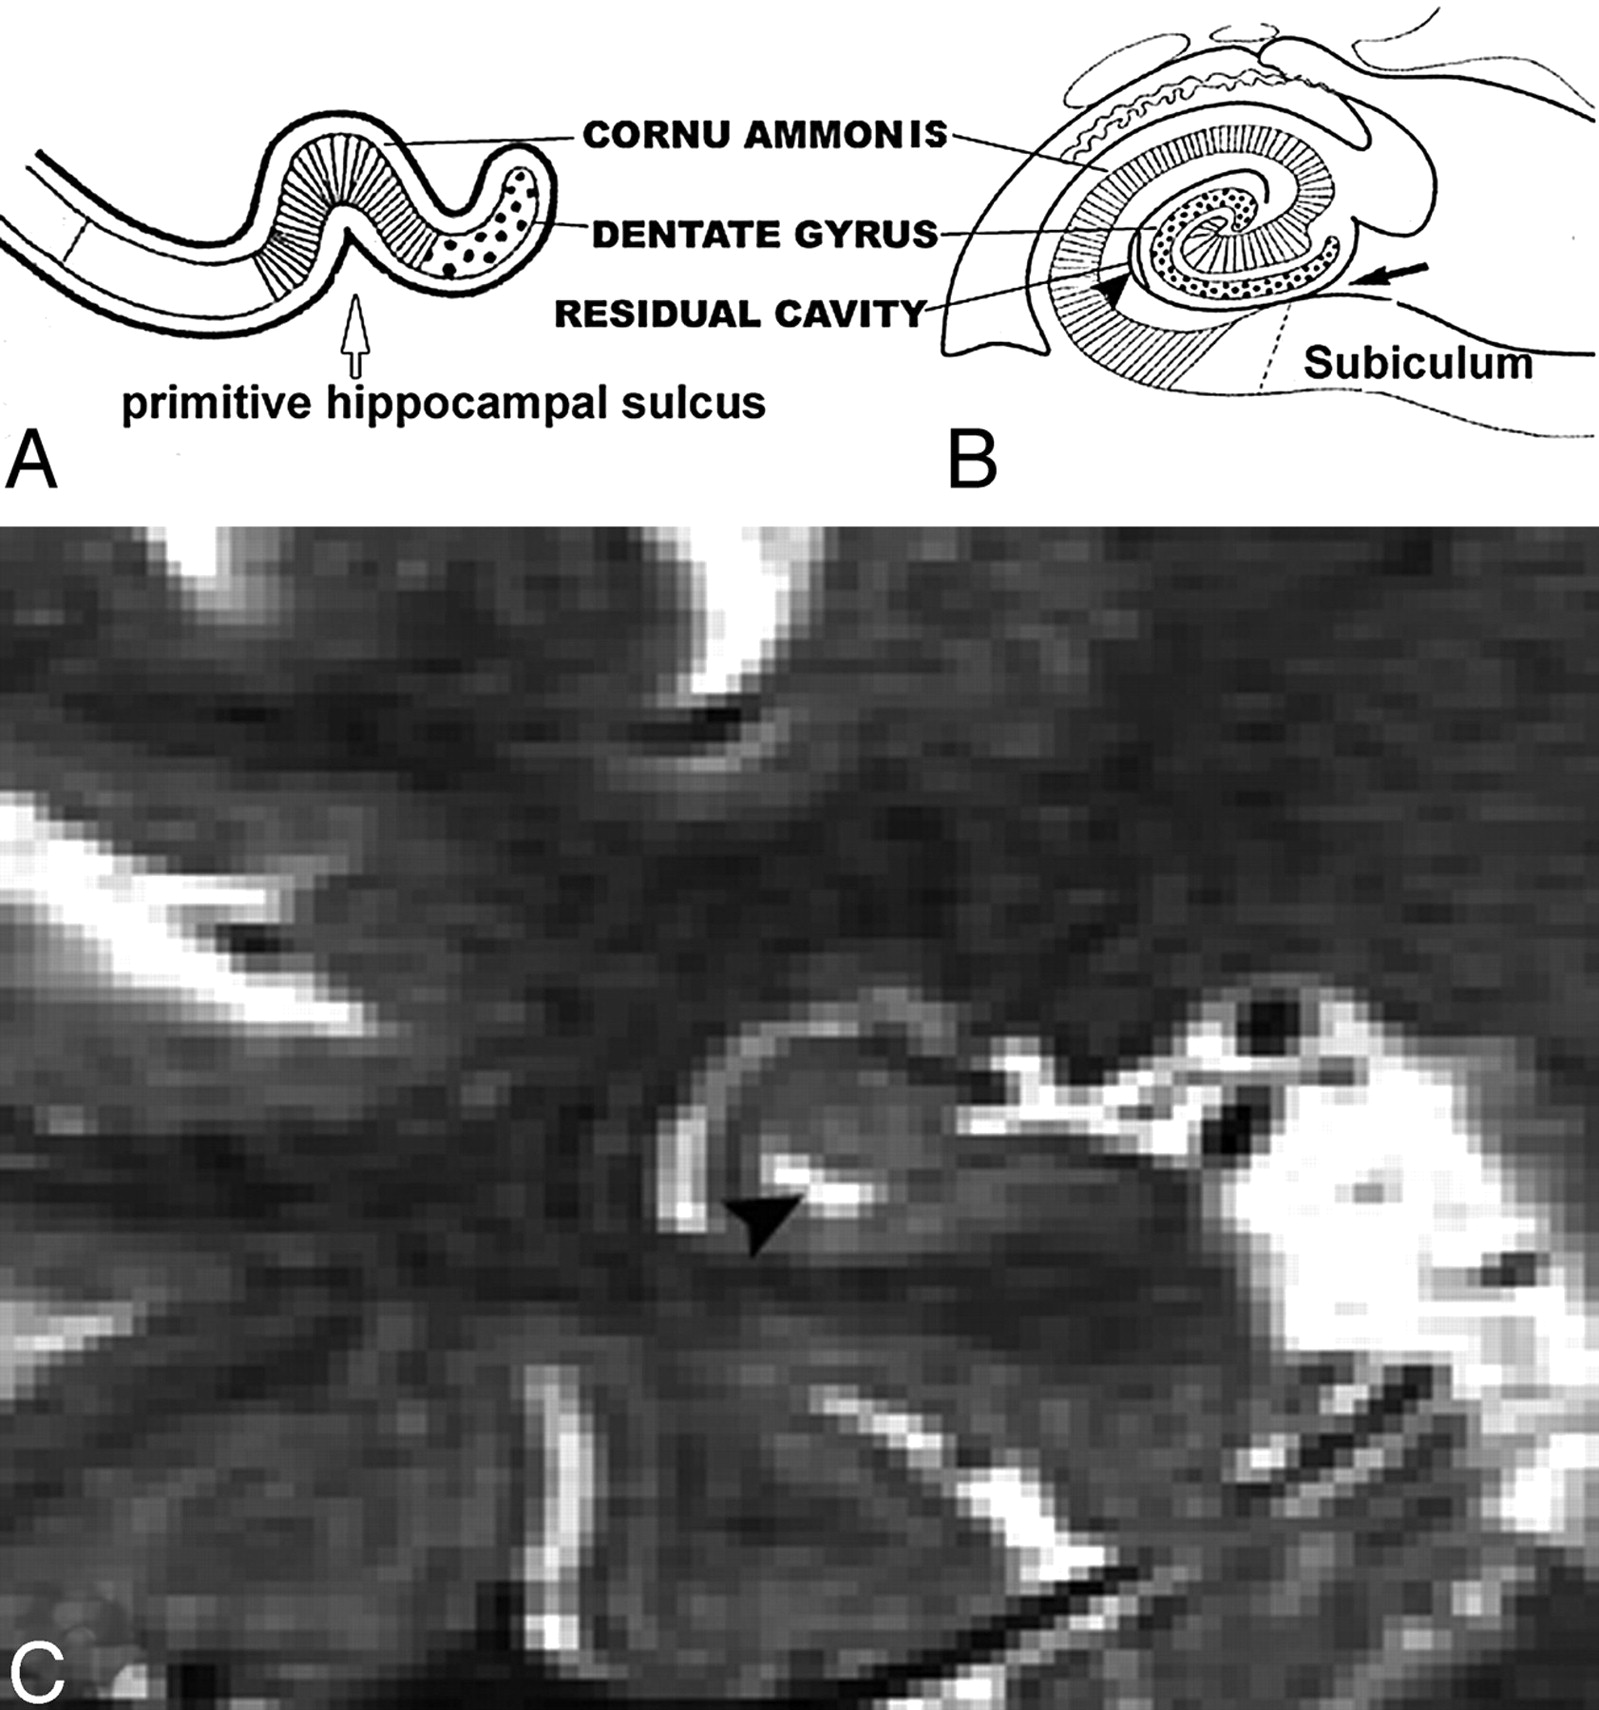

A and B, Normal anatomy of perihippocampal fissure.

A, Axial diagram showing the structure of perihippocampal fissures (PHF).

B, Coronal diagram showing the structure of PHF.

Black arrows, PHF; black arrowhead, hippocampal fissure; white arrowhead, choroidal fissure; curved arrow, transverse fissure of Bichat); H, hippocampus; S, subiculum; AC, ambient cistern.

According to Duvernoy,5 at the embryonic stage, the cornu ammonis and dentate gyrus are continuous. The growing cornu ammonis increasingly bulges into the ventricular cavity (Fig 11). The primitive cornu ammonis and dentate gyrus are inverted and rolled up, so a deep cleft, the primitive hippocampal sulcus, is formed between them. This is followed by fusion of the cornu ammonis and dentate gyrus, fusion of the subiculum and dentate gyrus, and closure of the largest portion of the sulcus. This results in a residual shallow groove, the hippocampal fissure. The remnant of the primitive hippocampal sulcus is the HSC (Fig. 12).5,6 The enlargement PHF is highly correlated with hippocampal atrophy.7-11 These dilated sulci may look like cavities on some cross-section of MR imaging. These CSF spaces in hippocampus need to be distinguished, because they often form part of the clinical radiologic impression of hippocampal atrophy. Errors are common, because the anatomy can be readily misidentified.12 The key to differentiating HSC from the uncal sulcus and PHF is location. Our data show that HSC are more lateral to both PHF and the uncal sulcus and distributed along the vestigial primary hippocampal sulcus close to the ventricular margins. Another important anatomical factor is the CSF channels.

Images derived from the human hippocampus (Duvernoy, 1988)5.

A, Six-week-old embryo. Open arrow shows the primitive hippocampal sulcus.

B, Adult. Black arrow shows the hippocampal fissure; arrowhead shows residual cavity.

C, T2 coronal MR image was obtained from a 67-year-old female normal control (NC) patient. Arrowhead shows the same shape hippocampal sulcus residual cavity (HSC) as in B.

T2 MR imaging (A) and the corresponding postmortem gross specimen (B) from an 86-year-old woman with Alzheimer disease (AD), showing a crescent-shaped HSC (arrowhead) and an enlarged uncal sulcus (arrow).